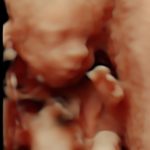

4D/5D/HD Ultrasound Gallery

Gallery